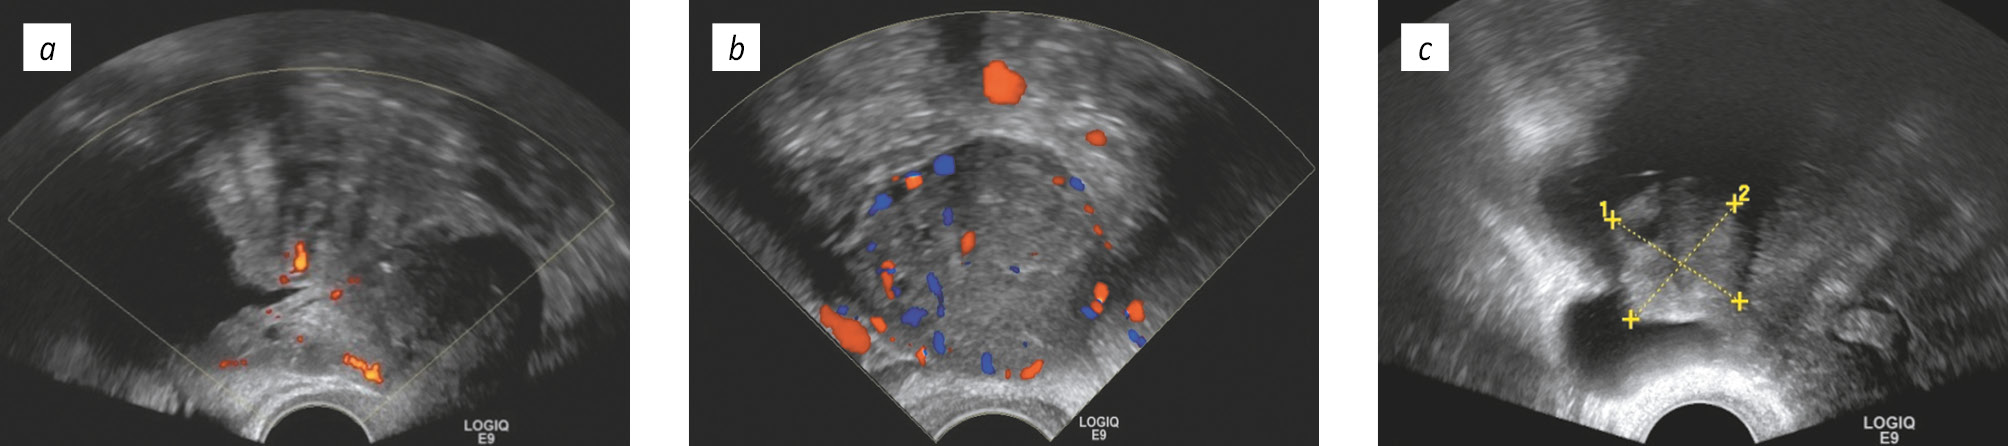

К группе новообразований яичника с высоким риском злокачественности относят васкуляризированные новообразования солидной или преимущественно солидной структуры, содержащие множественные васкуляризированные перегородки (>3 мм) и папиллярные разрастания на стенках в количестве более четырех (рис. 7). Однокамерные или многокамерные кистозные новообразования с солидным компонентом или преимущественно солидные (более чем на 80 %) относятся к образованиям с высоким риском пограничной опухоли или эпителиального РЯ [25, 26]. При обнаружении новообразования, имеющего вышеописанные УЗ-признаки, необходима консультация онкогинеколога и маршрутизация пациентки в стационар онкологического профиля [2].

Рис. 7. Новообразования яичника с высоким риском злокачественности: а — новообразование преимущественно солидной структуры с васкуляризацией при цветном допплеровском картировании; b — солидное гиперваскуляризированное новообразование яичника; c — многокамерное кистозное образование с солидным компонентом

Fig. 7. Ovarian neoplasms with high risk of malignancy: а — neoplasm of predominantly solid structure with vascularization (with color Doppler mapping); b — solid hypervascular neoplasm of the ovary; c — multiloculated cystic lesion with a solid component